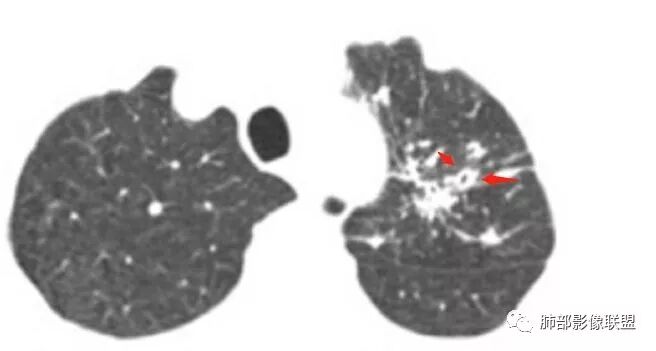

多发结节、斑片,大树芽征,沿支气管血管束分布

问个问题:哪些病变会此起彼伏?空洞+树芽征?

一般:血管炎、过敏、曲霉菌、寄生虫、OP

结核、NTM此起彼伏的少

曲霉菌不支持,空洞内面太干净了

我倒是怀疑血管炎